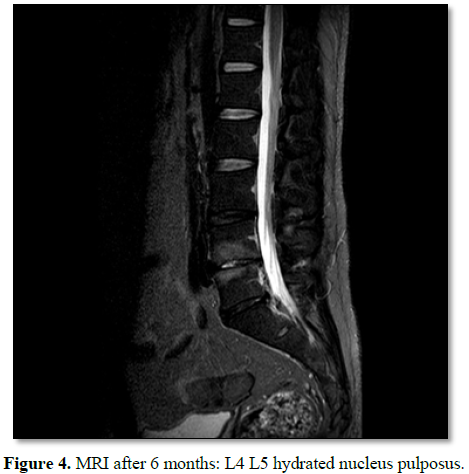

The pathology

identical to that performed in any percutaneous lumbar procedure is monitored (Figure

4).